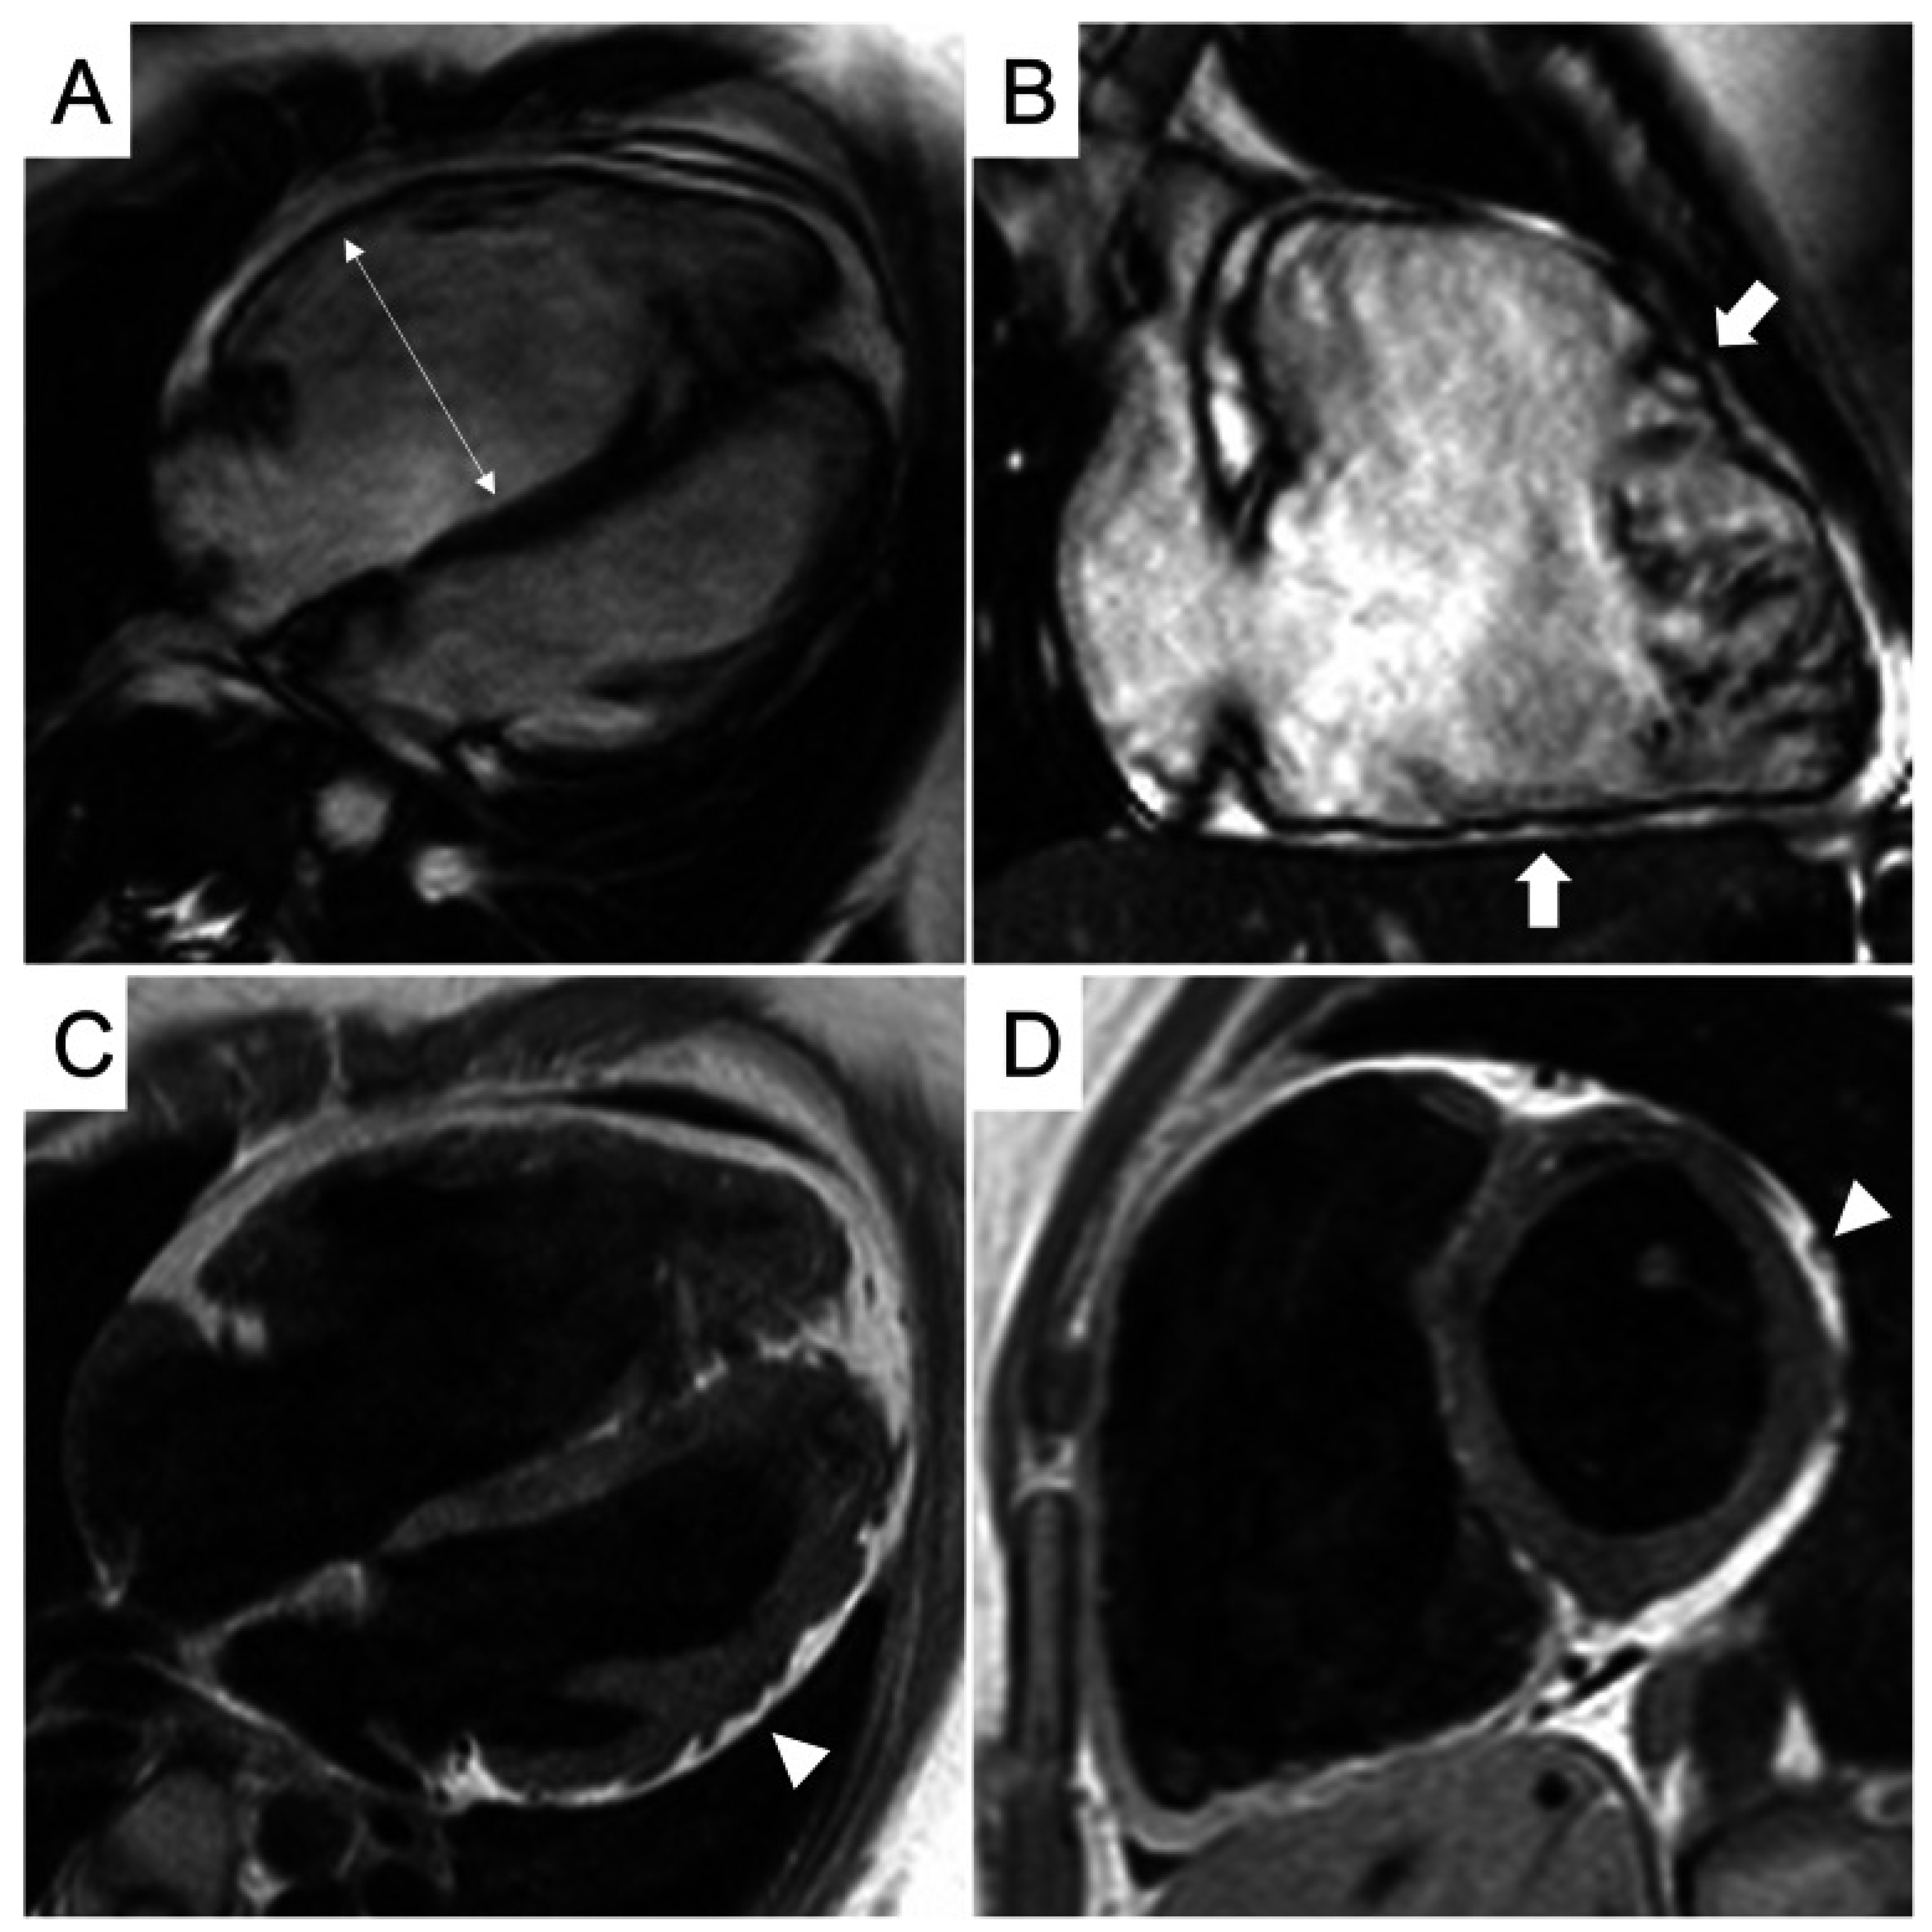

Characteristic CMR findings are the following (Figure 11):

- Subtle Tissue Changes: A hallmark of ICI myocarditis is the frequent absence of classic LLC criteria. LGE is present in less than 50% of cases, and T2-weighted STIR images may be normal [56].

- Key Role of Mapping: Elevated native T1 mapping is the most sensitive CMR parameter for detecting ICI myocarditis, often showing global elevation even in the absence of LGE. T2 mapping may be less consistently elevated [57,58].

- Prognostic Value: The presence of septal LGE and globally elevated native T1 are independent predictors of MACEs [59].

Figure 11.

Multi-contrast cardiovascular magnetic resonance image panel in patient with immune checkpoint inhibitor myocarditis. (A) T2-weighted SPAIR, (B) T2 mapping, (C) native T1 mapping, (D,E) phase-sensitive inversion recovery late gadolinium enhancement imaging, and (F) cine steady-state free precession. Focal basal myocardial edema (block arrow), focal late gadolinium enhancement (arrowheads), moderate pericardial effusion (*), and mild bilateral pleural effusion (arrows) are demonstrated. Reproduced from: Wintersperger, B.J., et al. (2022) [58]. Licensed under CC BY-NC 4.0 (https://creativecommons.org/licenses/by-nc/4.0/ accessed on 15 December 2025).